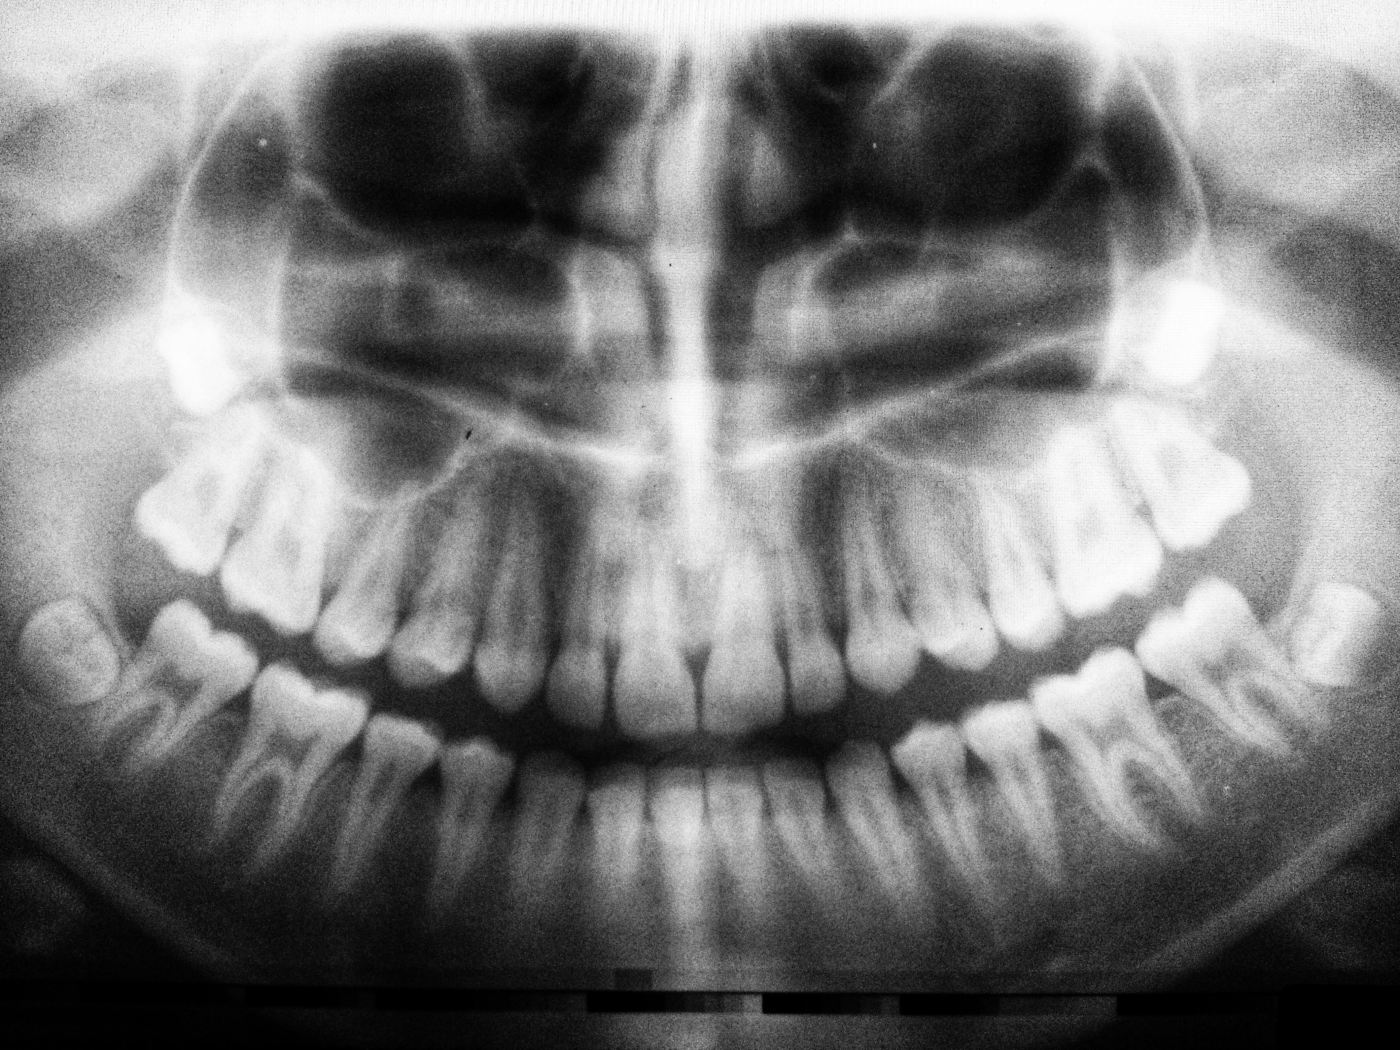

Weisheitszähne OP

Alle vier, durch die Hand eines Arztes, mittels eines metallenen Werkzeugs, aus meinem Kiefer, auf den Tisch gelegt.